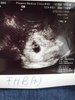

gratulacje mamusia rosnijcie zdrowoZobacz załącznik 891352kochane jest dobrze, widzialam kropeczke i bijace serducho! [emoji173]️

Zobacz załącznik 891352kochane jest dobrze, widzialam kropeczke i bijace serducho! [emoji173]️

Super!♡♡♡ Jeszcze raz gratulacje. Rośnijcie zdrowo :*Zobacz załącznik 891352kochane jest dobrze, widzialam kropeczke i bijace serducho! [emoji173]️